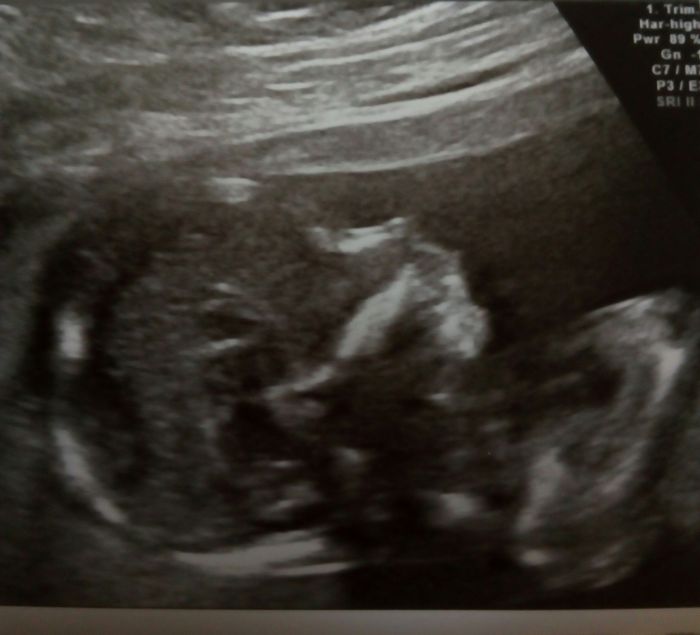

Ahojky, tak sse hlásím po kontrolách, včera jsme byla u svého doktora a vše ok, jen maličká nechtěla moc spolupracovat pořád na nás vystrkovala záda asi se styděla :-) takže zkontroloval co se dalo, chtěl udělat i foto 3d ale nebylo fakt nic vydět :-( takže snad příště, máme skoro 11cm .-) fotečky přikládám. U genetičk taky vše v pořádku i ostatní výsledky po odběru klků ok, tak se mi ulevilo. No a dneska jsme byla u Apolináře na kontrole po tom odběru, udělali mi podrobný ultrazvuk a tak jsme viděla všechno - hlavu, oči, žaludek, pusu, ruce i s kostičkama, močový měchýř...tý jo koukla jsme jak divá :-) doktor byl super všechno mi vysvětlil a popsal a moc hezky jsme si i popovídali :-)

Tak se hlásím z kontroly na genetice a podrobný ultrazvuk vše vypadá v pořádku. Po odběru choriovych klku jse vše v pohodě. Žádný problém tam není. Miminko v pořádku i ten tok pupečníku je lepší po těch tabletkach. Tak jsem šťastná jen se nechtěla nechat vyfotit celá. Tak jen z prifilu